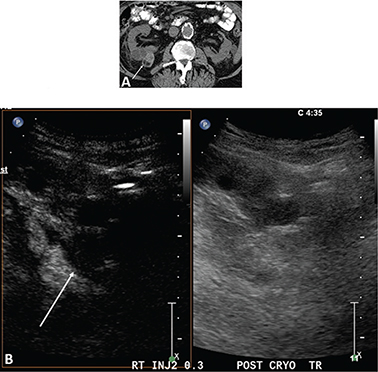

Occasionally a complete ablation cannot be obtained. This is often from significant blood flow to the mass or the mass adjacent to the collection system which acts as heat sinks and does not allow for adequate temperature to ablate the tumor. Figure 5 demonstrates a renal mass on the B-mode image (A) and the CEUS image (B). Immediately post-RFA, the B-mode (C) and CEUS (D) demonstrate minimal ablation of the tumor.

Figure 5. Failed ablation. Patient has history of prior left nephrectomy for RCC and presented with right renal mass. (A) Gray scale image of mass (arrow) pre-ablation. (B) CEUS demonstrating increased flow in tumor (arrow) at inferior pole of right kidney. (C) Gray scale image post-RFA of the mass (arrow). (D) CEUS post-RFA demonstrating flow throughout the tumor (arrow), indicating failed RFA.

Figure 6 demonstrates the advantage of CEUS over CT. Because CEUS has a contrast-only image, small amounts of enhancement are easily identified. On CT (as well as MRI) there is signal from the associated soft tissues, making it difficult to identify small amounts of enhancement.

Figure 6. Images 6 months post-RFA of an RCC. (A) CT scan without contrast in this patient with renal failure. The ablated RCC (arrows) has significant attenuation making it difficult to determine if there is residual tumor. Even if contrast is administered, the background tissue makes it difficult to identify small areas of enhancement. (B) CEUS scan at the same 6-month post-RFA time point as the CT in (A). Ultrasound contrast agents can be used in patients with renal failure. Note that the excellent tissue suppression of CEUS allows for a contrast-only image, making it easy to see that there is no enhancement and no residual or recurrent tumor.